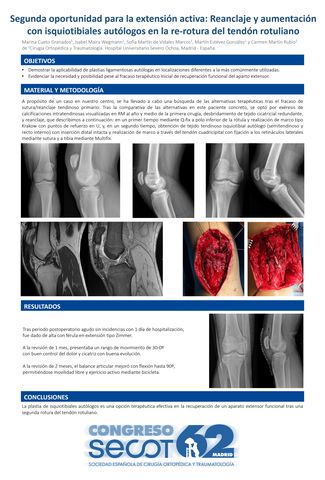

Segunda oportunidad para la extensión activa: Reanclaje y aumentación con isquiotibiales autólogos en la re-rotura del tendón rotuliano

MARINA CUETO GRANADOS, ISABEL MAIRA WEGMANN , SOFÍA MARTÍN DE VIDALES MARCOS, CARMEN MARTÍN RUBIO, MARTÍN ESTÉVEZ GONZÁLEZ